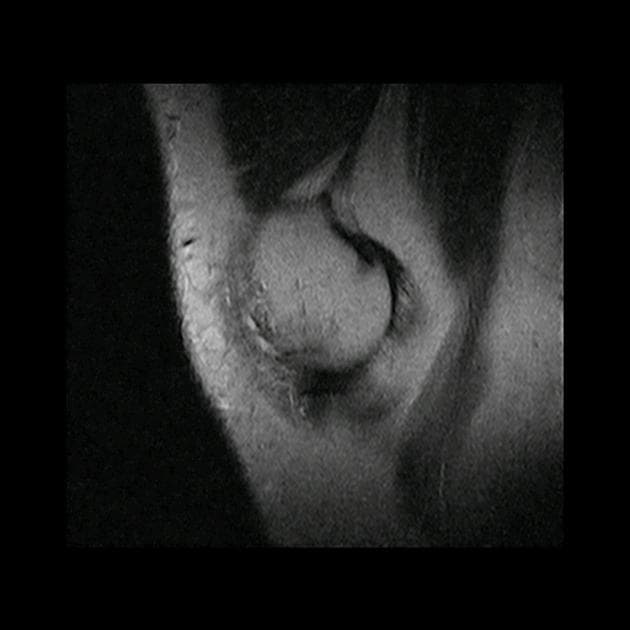

- Đứt thân và sừng sau của sụn chêm bên, gây ra hiện tượng một phần đáng kể của sụn chêm bị lật về phía trước và vào trong, nằm trong khe gian lồi cầu.

- Ngoài ra, thấy dấu hiệu "tam giác kép" (double delta sign) ở phía trước.

Tháp mạc gối lật ngược (flipped meniscus) là một dạng rách dạng xô (bucket handle tear), trong đó một phần lớn của sụn chêm bị lật và nằm kề sừng trước, dẫn đến tạo thành khoảng trống tại vị trí cho (donor site).

- "Dấu hiệu 'tam giác kép' là phát hiện cộng hưởng từ quan trọng trong tháp mạc gối lật ngược, biểu hiện mảnh sụn di lệch nằm kề sừng trước, tạo thành hai cấu trúc hình tam giác."

Tháp mạc gối lật ngược là một dạng đặc biệt của rách dạng xô, thường gặp ở sụn chêm bên. Tình trạng này xảy ra khi một vết rách dọc dọc cho phép một mảnh lớn của sụn chêm—thường là thân và sừng sau—di lệch về phía trước và vào trong vào khe gian lồi cầu. Sự di lệch này dẫn đến 'dấu hiệu sụn chêm ảo', khi giường sụn chêm nguyên bản trông trống rỗng trên hình ảnh cắt dọc. Mảnh sụn di lệch nằm kề sừng trước, tạo thành 'dấu hiệu tam giác kép'—hai cấu trúc hình tam giác riêng biệt có cường độ tín hiệu thấp, đại diện cho sừng trước bình thường và mảnh sụn bị lật. Các phát hiện đi kèm như tổn thương dập xương, dịch khớp và căng giãn dây chằng thường gặp do cơ chế chấn thương. Việc nhận diện sớm trên cộng hưởng từ rất quan trọng để lên kế hoạch phẫu thuật, vì tổn thương này thường cần được giảm chỉnh và sửa chữa nội soi.